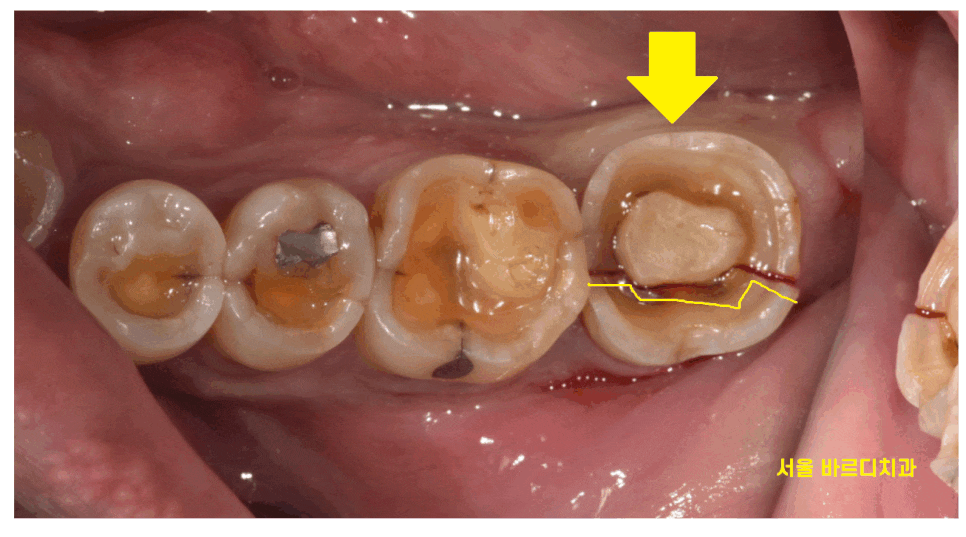

왼쪽 아래가 씹을 때 불편해요

증상으로 망월동 치과를 내원하셨습니다.

치아가 많이 닳아지다 보니

신경 부분이 표면으로 노출되어

씹을 때마다 자극을 주었습니다.